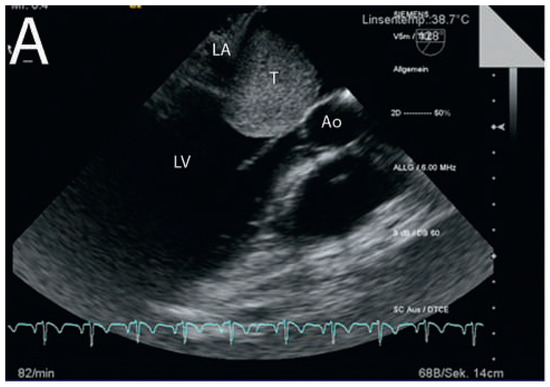

Dyspnoea and Impaired Ventricular Filling Due to Infiltration of the Left Atrium with a Lung Adenocarcinoma

by Federico Moccetti, Björn Müller-Edenborn, Walter Weder and Urs Eriksson

Cardiovasc. Med. 2012, 15(9), 261; https://doi.org/10.4414/cvm.2012.01691 - 26 Sep 2012

Viewed by 125

A 59-year-old patient without a history of heart failure complained of progressive dyspnoea of two weeks’ duration [...] Full article

Show Figures

Figure 1